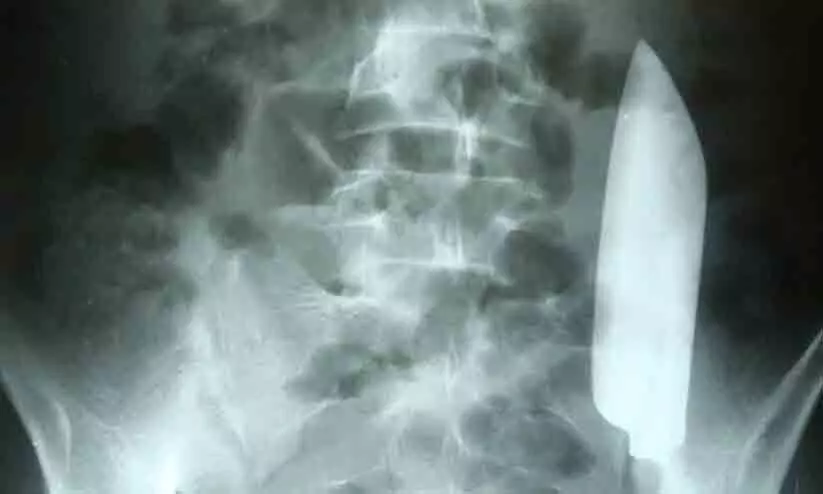

text_fieldsകാഠ്മണ്ഡു: കടുത്ത വയറുവേദനയുമായെ ആശുപത്രിയിലെത്തിയ 22 കാരന്റെ വയറ്റിൽ നിന്ന് പുറത്തെടുത്തത് 15 സെ.മി വലിപ്പമുള്ള കത്തി. ദിവസങ്ങൾക്ക് മുമ്പ് യുവാവിന് കത്തിക്കുത്തേറ്റിരുന്നതായി ന്യൂസ് വീക്ക് റിപ്പോർട്ട് ചെയ്തു. എന്നാൽ കത്തി വയറ്റിനുള്ളിലുണ്ടെന്ന കാര്യം ആരും സംശയിച്ചിരുന്നില്ല.

ഡോക്ടർ ശരീരം സൂക്ഷ്മമായി നിരീക്ഷിച്ചപ്പോഴാണ് മുറിവിന്റെ പാട് കണ്ടത്. തുടർന്ന് എക്സ്റെ എടുത്തപ്പോൾ വയറ്റിൽ കത്തിയുള്ളതായി കണ്ടെത്തി. ഇത് വയറിന്റെ നിന്ന് ഒരുഭാഗത്ത് നിന്ന് മറ്റൊരു ഭാഗത്തേക്ക് മാറുമ്പോഴാണ് വേദന അനുഭവപ്പെട്ടത്. ശസ്ത്രക്രിയ വഴിയാണ്കത്തി പുറത്തെടുത്തത്.